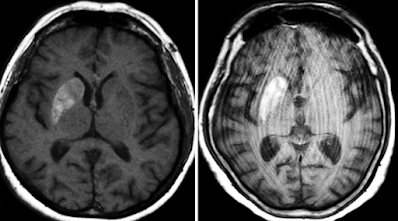

MRI (preferred modality):

• T1-weighted images: Hyperintensity in the contralateral putamen and/or caudate nucleus.

• T2-weighted/FLAIR: Often normal or mildly hypointense.

• DWI/ADC: Usually no diffusion restriction, helping distinguish from acute infarct.

Key radiologic term: “Diabetic striatopathy” refers to the imaging hallmark of striatal hyperintensity in nonketotic hyperglycemia.

CT Findings

• Often normal, but may show hyperdensity in the basal ganglia.

MRI Findings

• T1-weighted images: High signal intensity in the basal ganglia, especially the caudate nucleus and putamen (with or without globus pallidus involvement).

• T2/FLAIR: Often normal or only mildly hyperintense—less sensitive.

• No contrast enhancement or restricted diffusion.

• Susceptibility imaging (SWI/GRE): Usually normal in early stages; may show low signal intensity later due to metal deposition (e.g., manganese or iron).

Differential Diagnosis

• Wilson’s disease

• Hypertensive hemorrhage

• Benign calcification

• Carbon monoxide poisoning

• Manganese deposition in hepatic encephalopathy

• Nonketotic hyperglycemic hemichorea (most consistent)

Diagnosis

• Nonketotic Hyperglycemic Hemichorea (NKH-HC)